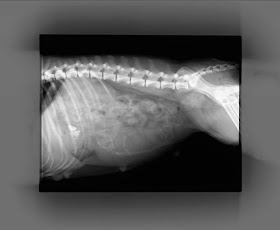

| Väntar!!! En!!!? |